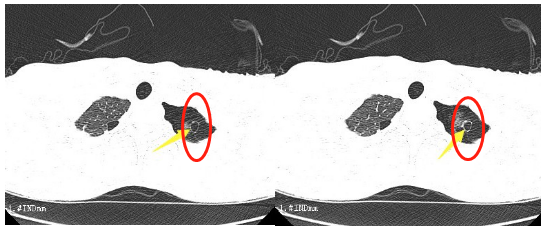

這段時間,16歲的小王突然出現(xiàn)了胸悶的癥狀,持續(xù)一周都不見好轉(zhuǎn)。到我院胸心外科檢查后,胸片提示左側(cè)液氣胸,積氣為主,結(jié)合患者術(shù)前CT檢查情況,考慮為肺大泡破裂引起的氣胸。

“肺大泡,也叫肺大皰,是指由于各種原因?qū)е路闻萸粌?nèi)壓力升高,肺泡壁破裂,互相融合,在肺組織形成的含氣囊腔。”胸心外科醫(yī)生鄧意平說,肺大泡的增大或增多,會使肺功能發(fā)生障礙并逐漸出現(xiàn)癥狀,像小王這樣年紀輕輕的小伙子也可能出現(xiàn)胸悶、氣短等癥狀。